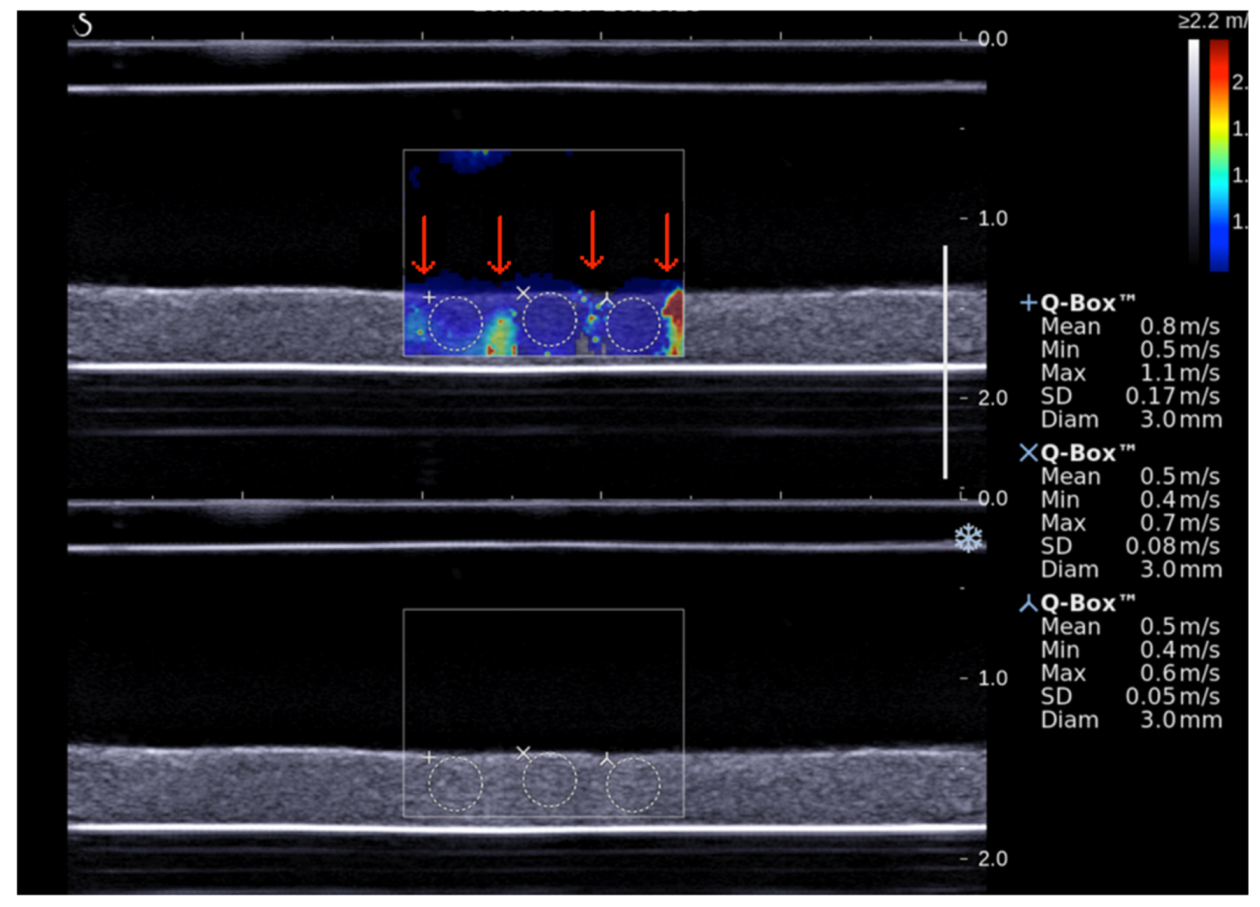

2.6. Shear Wave Elastography Imaging

Aixplorer® ultrasound scanner with an L15-4 probe (4–15 MHz, 1 mm axial resolution) [13,18] was employed to acquire blood clot elastographic images every 10 min for 60 min. After acquisition, elastic properties of the blood clot were quantitatively analyzed using the Aixplorer® software. Shear wave speed (SWS) was measured for each region of interest (ROI) defined in the area exposed to the STL while avoiding ultrasound beam push artifacts (red arrows in Figure 3). Such artifacts were described by Lin et al. [19]. The Young modulus can be deduced from SWS for each ROI according the equation [20]:

Figure 3.

Shear wave ultrasound imaging of blood clot. Red arrows show ultrasound beam push artifacts. SWS was measured with Q-box® software.